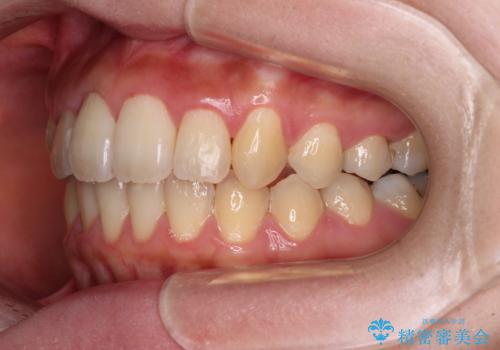

- 捻れた前歯が飛び出しており、口が閉じにくいとのことで来院された患者様です。

出っ歯というわけではないものの、前歯の捻転により口唇が押し出されている状態でした。

親知らずを抜去し、歯列全体を後方に移動させつつ、IPR(歯と歯の間を削る)でスペースを獲得し、インビザラインを用いて叢生を解消しながら前歯の突出を改善することとしました。